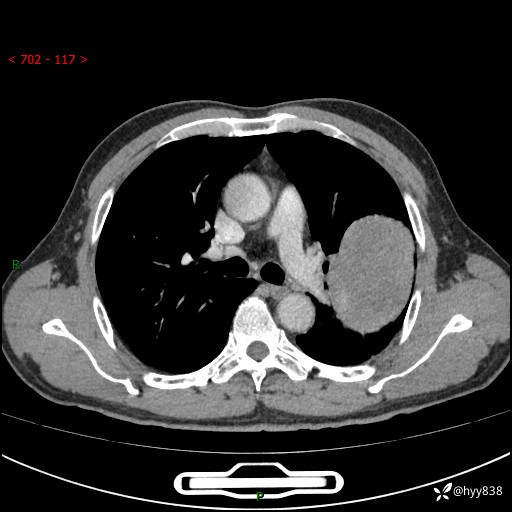

68岁/男,发现左下肺占位5天。如此大的肿块,患者竟然没有症状---结果公布~

【患者信息】:68岁/男

【主诉】:检查发现左下肺占位5天。

【现病史及既往史】:患者于4天前外院行“经尿道钬激光碎石术”,住院期间胸部CT检查发现左下肺肿块,患者平素无明显咳嗽咳痰,无心慌、胸闷、胸痛、呼吸困难、低热、盗汗,无头痛、头晕,无腹痛、腹胀等不适,现患者为求进一步治疗,遂来我院就诊,以“左下肺肿块”收入我科。 患者自起病以来,精神可,睡眠可,饮食可,大小便正常,体重无明显改变。

【检查】:胸部CT增强扫描